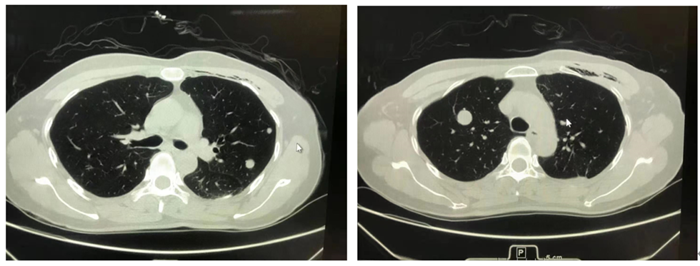

图1 图2

图1、2胸部CT图片分别显示左、右侧肺部(黑色)类圆形灰白结节,好似“夜空中的一轮圆月”

王志敢主任医师介绍,肺部良性转移性平滑肌瘤(PBML)主要发生于育龄期有子宫肌瘤或子宫切除病史的女性。患者无特异性临床表现, CT表现为双侧肺部(黑色背景)多发大小不一类圆形结节(白色),具有一定特征,可以形象地称为“夜空中的一轮圆月”。偶尔可为肺部单发结节。罕见情况下可发生于心血管、骨骼肌、淋巴结等部位。该肿瘤因生长缓慢,不会严重影响肺功能,可带瘤生存数十年,因此极易漏诊。自首次报道该肿瘤至2020年6月,有人在WJCC(World Journalof Clinical Cases)杂志上统计全球仅有100例。近10年来,立博体育